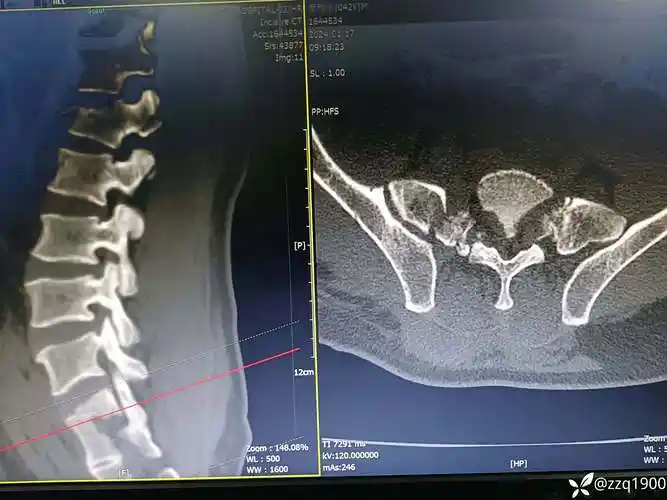

骶骨骨折

邹女士骨盆左侧受暴力致骨折移位(3d影像):①后环骶骨骨折,骶髂冠节

病例分享腰椎骶骨骨折如何处理

占整个骨盆功能60%,骶骨经过骶孔骨折或骶髂关节损伤的治疗效果对骨盆